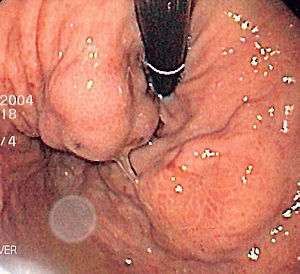

| Isolated gastric varices of Sarin classification IGV-1 seen on gastroscopy in a patient with portal hypertension | |

Diagnosis of gastric varices is often made at the time of upper endoscopy.

The Sarin classification of gastric varices identifies four different anatomical types of gastric varices, which differ in terms of treatment modalities.